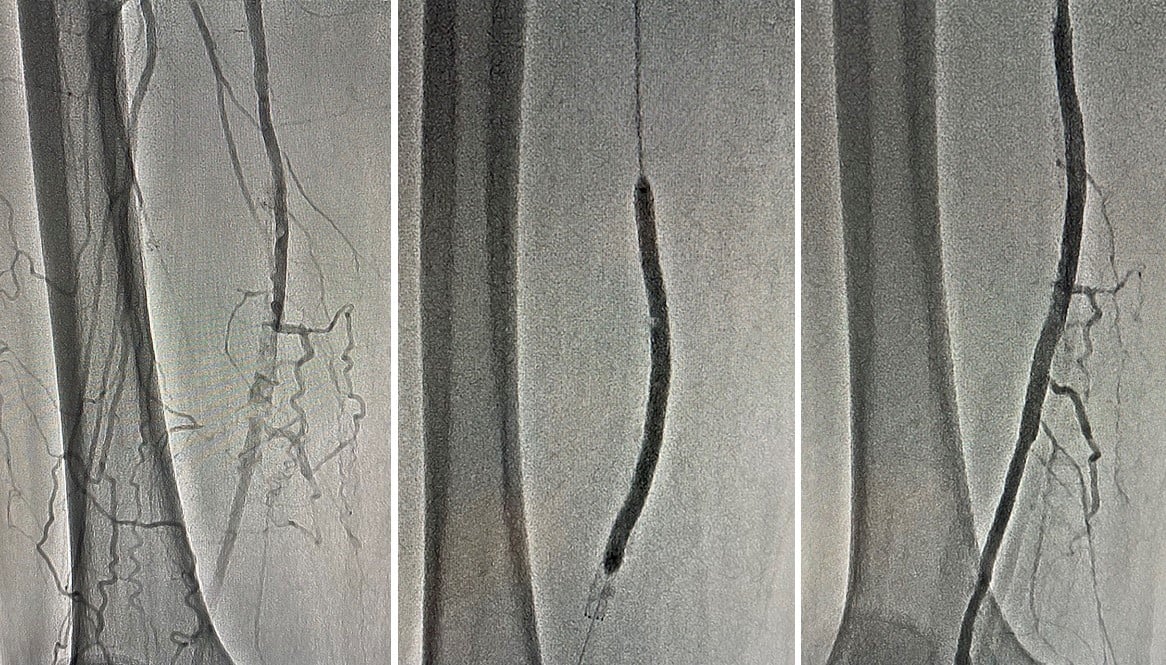

Лікарі Ковельського МТМО успішно прооперували чоловіка, який міг втратити ноги.

Пацієнт 1960 року народження звернувся до судинних хірургів зі скаргами на виражені болі у обох нижніх кінцівках, що значно посилювались при ходьбі до 100 метрів, порушення сну та переміжну кульгавість, що турбували його тривалий час.

Після проведення ангіографії нижніх кінцівок діагностовано субоклюзію та оклюзію дистальних відділів поверхневих стегнових артерій – 100% і 98%. Команда ендоваскулярних хірургів провела стентування обох артерій через проколи в паху.

Операція пройшла успішно. Лікарям вдалося повністю відновити кровотік в судинах та запобігти втраті обох кінцівок. Нині біль в ногах пацієнта не турбує. На третій день після операції його виписали з лікарні.